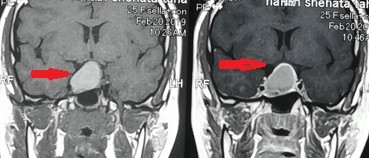

tumor of the base of the skull pressing on the right optic nerve